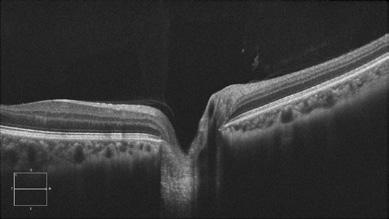

Le délai entre l’apparition des symptômes et le début de l’OHB et les observations du fond d’œil, notamment la présence d’une tache rouge cerise, la modification de l’épaisseur maculaire et le degré de désorganisation des couches internes de la rétine, apparaissent comme des marqueurs cliniques permettant de prédire la réponse à l’OHB40

Hadanny et coll. ont proposé que l’utilisation d’une tache rouge cerise visible comme indicateur physiologique d’une efficacité réduite de l’OHB soit plus prédictive que le délai d’apparition de l’ORC68. D’autres prédicteurs négatifs de la réussite de l’OHB sont l’architecture rétinienne pathologique et l’épaississement maculaire, qui sont tous deux des signes directs de la gravité et de la progression de l’ischémie69